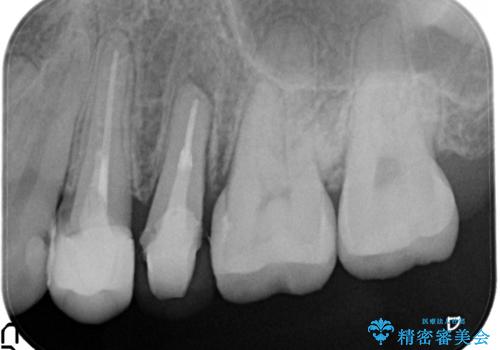

歯を部分矯正で引き上げて、虫歯を徹底的に取り除き、適合の良いかぶせ物を装着する計画としました。